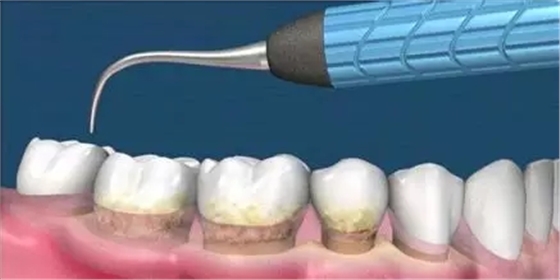

這是牙周病常規(guī)的治療方法,清除或控制臨床炎癥和致病因素,去除病因,消除炎癥。包括口腔衛(wèi)生宣教、充填齲洞、口腔潔治刮治、牙體牙髓治療、咬合調(diào)整、去除不良修復(fù)體、藥物治療(輔助手段,局部用藥效果好)、拔除治療效果不佳的牙周病患牙等。

牙周炎發(fā)展到一定階段時(shí),僅采用基礎(chǔ)治療難以取得較好療效,必須通過(guò)適時(shí)而合宜的手術(shù)治療挽救患牙,才能保持牙周組織健康,延長(zhǎng)患牙在口腔內(nèi)的壽命,維持牙列的完整性,促進(jìn)全身健康。其手段包括齦下刮治、根面平整、牙周翻瓣術(shù)、牙齦切除術(shù)、牙周夾板固定術(shù)等。